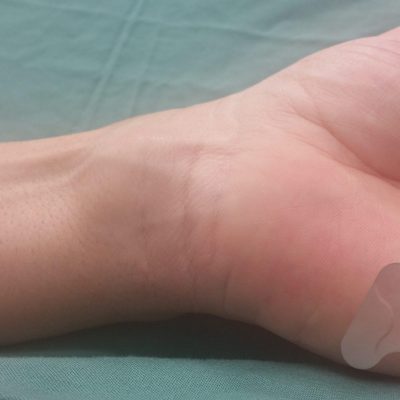

Ganglions are fluid filled cysts that arise from a joint or tendon. A small perforation in a ligament or tendon sheath can create a one way valve where fluid can feed the cyst but not let fluid back out. This can cause a local swelling of a few mm or a 1-2 cm or more depending on the location. Ganglions can be painless or can cause pain and discomfort from pressure and irritation of the surrounding tissues. Ganglions are very common and often found on the back of the wrist, palm of the hand or near the nail, at the DIPJ, but can arise in other parts of the hand and wrist. When they are not causing problems they can be left untreated without risk of long term damage or deterioration and can fluctuate in size or resolve spontaneously.